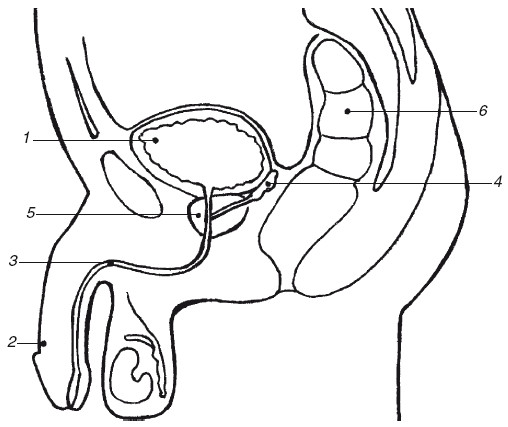

Анатомическое расположение предстательной железы

1 – мочевой пузырь; 2 – половой член; 3 – мочеиспускательный канал (уретра); 4 – семенные пузырьки; 5 – предстательная железа; 6 – задний проход